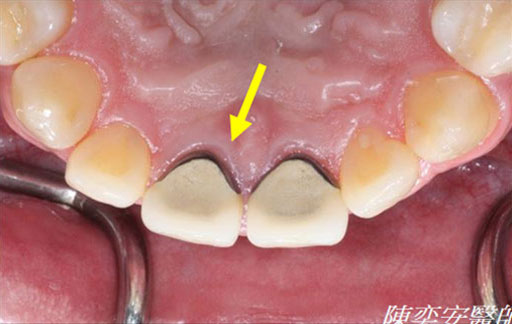

治療後

恢復健康牙齦

牙周再生成功